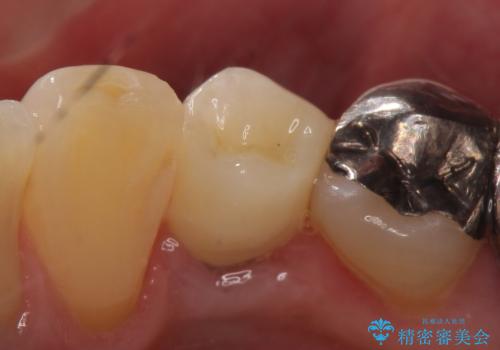

- 他院にて右下4番目の歯の再根管治療が必要だと言われた方の症例です。

再根管治療終了後、オールセラミッククラウンによる補綴を行いました。

今回用いたオールセラミッククラウンは、ジルコニアフレームという白い素材の上にセラミックを盛っているため審美性が非常に高いのが特徴です。

またジルコニアは人工ダイヤモンドの材料にも使われているほど高い強度を持っており、そのためオールセラミッククラウンは審美性だけでなく、奥歯やブリッジの補綴も可能とするクラウンです。